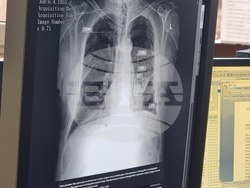

В отделението по образна диагностика на Многопрофилната болница за активно лечение „Рахила Ангелова“ в Перник бе внедрен изкуствен интелект (AI), съобщи пред журналисти директорът на болницата Явор Дренски. Инсталирането на софтуера приключи вчера, а през следващия месец предстои безплатна скринингова кампания за всички жители на областта.

Той посочи, че по време на кампанията изкуственият интелект ще анализира снимките, а при откриване на потенциален проблем ще се включи рентгенолог, който да уточни диагнозата и да насочи пациента за последващо лечение.

Дренски коментира, че AI системата има няколко основни приложения. Освен че подпомага обучението на младите специалисти, тя улеснява работата на рентгенолозите при прецизиране на диагнозата. Софтуерът ще позволява също провеждането на масови скрининги за ранно откриване на заболявания на белия дроб.

„Направата на рентгеновата снимка и разчитането ѝ ще става за минути. Това ще позволи повече хора да се прегледат бързо и ефективно“, допълни директорът на болницата в Перник.